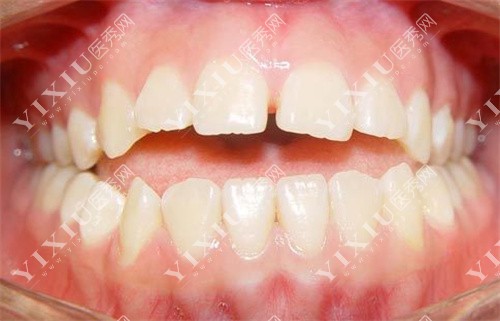

牙医回应:牙根太短能矫正牙齿吗,来看牙医如何矫正!-医秀网

图片尺寸500x321